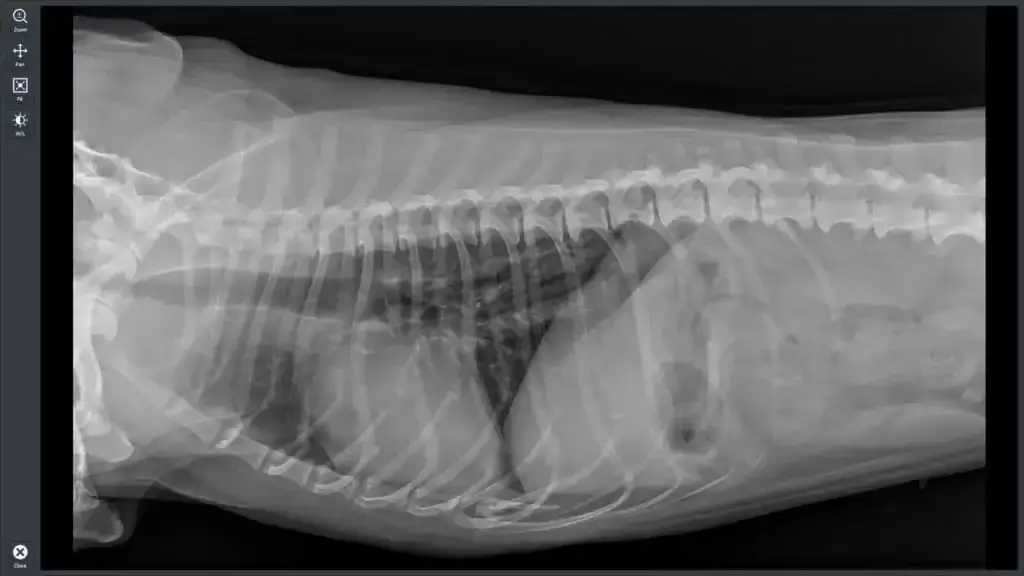

Średnie ceny prześwietlenia dla psów i kotów w Polsce różnią się w zależności od specyfiki badania. Dla psów, cena badania rentgenowskiego wynosi średnio około 223,30 zł, a dla kotów jest zbliżona. Przykładowo, prześwietlenie łapy psa może kosztować od 100 do 300 złotych, w zależności od kliniki i lokalizacji. Warto przed wizytą u weterynarza zapytać o szczegółową wycenę, aby uniknąć nieprzyjemnych niespodzianek związanych z kosztami.

W dużych miastach, takich jak Warszawa, Kraków i Wrocław, ceny prześwietlenia są zazwyczaj wyższe. W Warszawie koszt RTG dla psa wynosi od 220 do 254 zł, a dla kota od 200 do 240 zł. W Krakowie ceny wahają się od 200 do 254 zł dla psów, natomiast w Wrocławiu można spodziewać się kosztów od 180 do 254 zł. Te różnice w cenach mogą być znaczące, dlatego warto porównać oferty różnych klinik weterynaryjnych przed podjęciem decyzji.

| Miasto | Średni koszt RTG dla psa (zł) | Średni koszt RTG dla kota (zł) |

| Warszawa | 220 - 254 | 200 - 240 |

| Kraków | 200 - 254 | 180 - 230 |

| Wrocław | 180 - 254 | 170 - 220 |